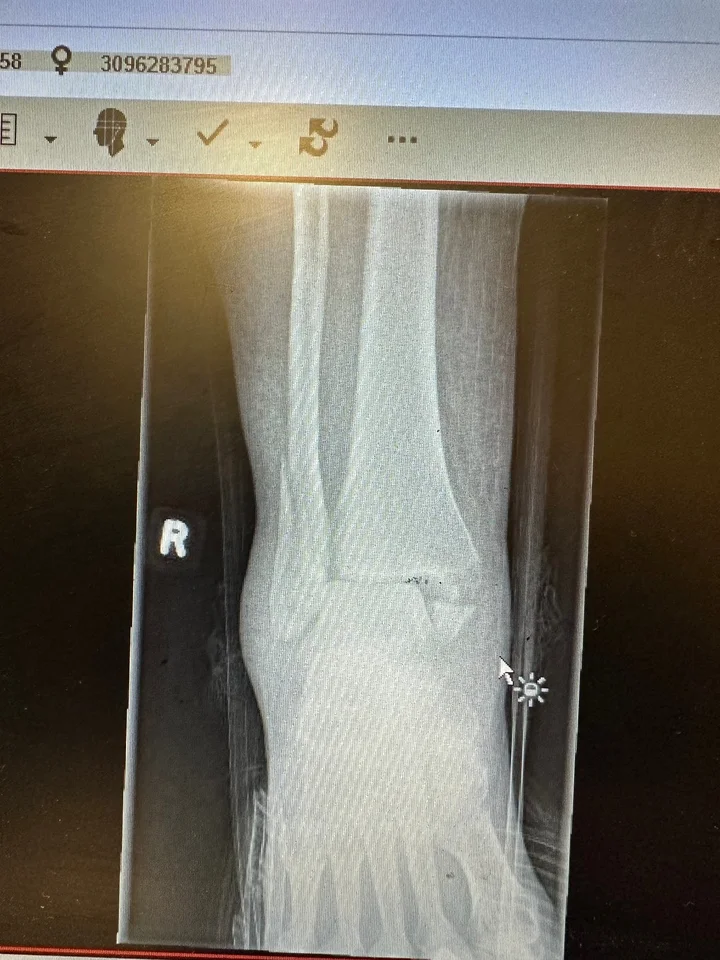

Easiest process and great company to deal with – Claim resolved within 6 weeks of accident and subsequent surgery Show details ·  1